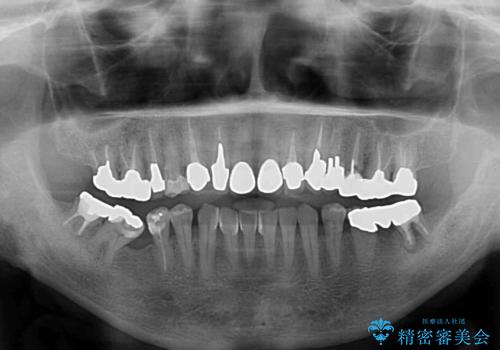

- 抜歯した歯や抜歯が必要と思われる歯を放置したため、奥歯に不快を感じているとのことで来院された患者様です。

右下は奥歯が抜歯したスペースを塞いでしまい、左下はブリッジの支台歯の1つが破折している状態でした。

また、下顎前歯にはスペースがあり、コンポジットレジンでスペースを閉じている状態だったので、前歯のスペースを解消しつつ、奥歯にスペースを獲得するよう矯正治療を行うこととしました。

並行して左下にはインプラントを埋入し、上顎臼歯部の気になる部分も根管治療などを進めて行き、矯正治療を終えると同時に補綴治療を行うこととしました。